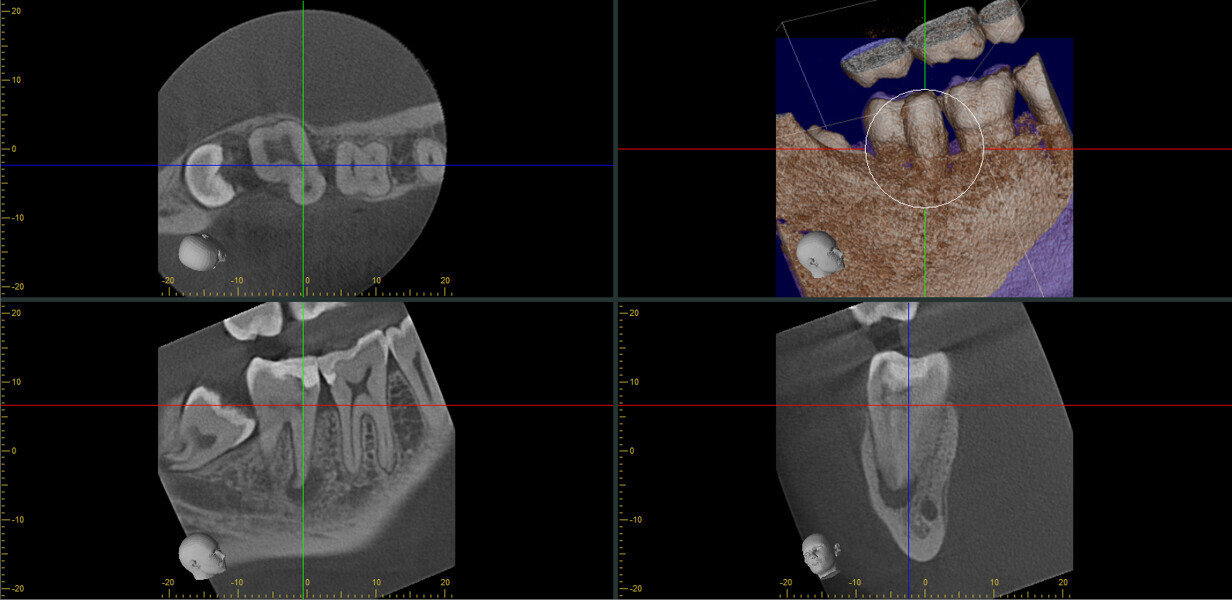

Fig. 17a: Case assisted with CBCT to determine anatomy pre-operatively. Note the multiple cross sections moving apically and the correlation to the 2-D view. Note also the conservative taper in relation to the root width. (Courtesy of Dr. Brett Gilbert)

Fig. 17b: Case assisted with CBCT to determine anatomy pre-operatively. Note the multiple cross sections moving apically and the correlation to the 2-D view. Note also the conservative taper in relation to the root width. (Courtesy of Dr. Brett Gilbert)

Fig. 17c: Case assisted with CBCT to determine anatomy pre-operatively. Note the multiple cross sections moving apically and the correlation to the 2-D view. Note also the conservative taper in relation to the root width. (Courtesy of Dr. Brett Gilbert)

Fig. 17d: Case assisted with CBCT to determine anatomy pre-operatively. Note the multiple cross sections moving apically and the correlation to the 2-D view. Note also the conservative taper in relation to the root width. (Courtesy of Dr. Brett Gilbert)

Fig. 17e: Case assisted with CBCT to determine anatomy pre-operatively. Note the multiple cross sections moving apically and the correlation to the 2-D view. Note also the conservative taper in relation to the root width. (Courtesy of Dr. Brett Gilbert)

Fig. 17f: Case assisted with CBCT to determine anatomy pre-operatively. Note the multiple cross sections moving apically and the correlation to the 2-D view. Note also the conservative taper in relation to the root width. (Courtesy of Dr. Brett Gilbert)